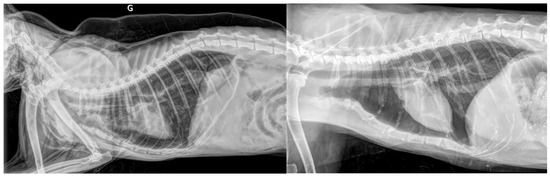

3.3. Results for Cats in Group C—Cardiac Origin

3.5. Results for the Cats in Group N—Neoplastic Origin